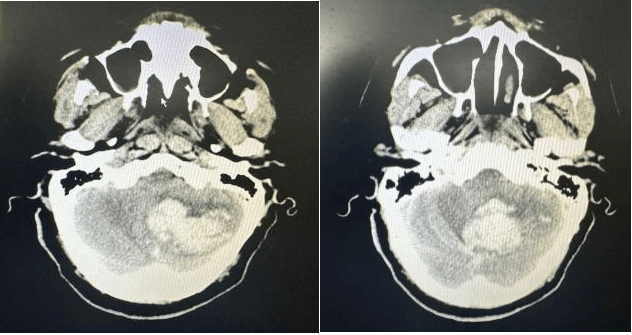

面对此例极危重患者,急诊医学科团队在患者到院第一时间立即启动最高级别卒中/脑出血救治绿色通道。紧急气管插管,同时建立静脉通路开通急救通道,在维持患者基础生命支持的同时,同步联系影像科。医学影像科“绿色通道”立即响应,CT扫描快速完成。神经外科值班医师火速阅片,明确诊断:小脑大量出血(37.3ml)破入第四脑室,脑疝形成、脑干受压、梗阻性脑积水。小脑出血量远超手术指征的警戒线,死亡率极高,每一分钟的延误,都可能意味着死亡和不可逆的脑干功能衰竭……

术前CT

术后CT